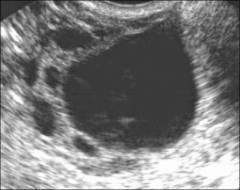

- УЗИ. Одна из наиболее информативных методик, которая позволяет осмотреть и оценить внутреннюю структуру яичника, обнаружить кисты. Ультразвуковое исследование при поликистозе проводится при помощи датчика, который вводится через влагалище.

Фото: УЗИ-картина фолликулярной кисты яичника. Киста представляет собой полость больших размеров, также визуализируются нормальные фолликулы яичника.